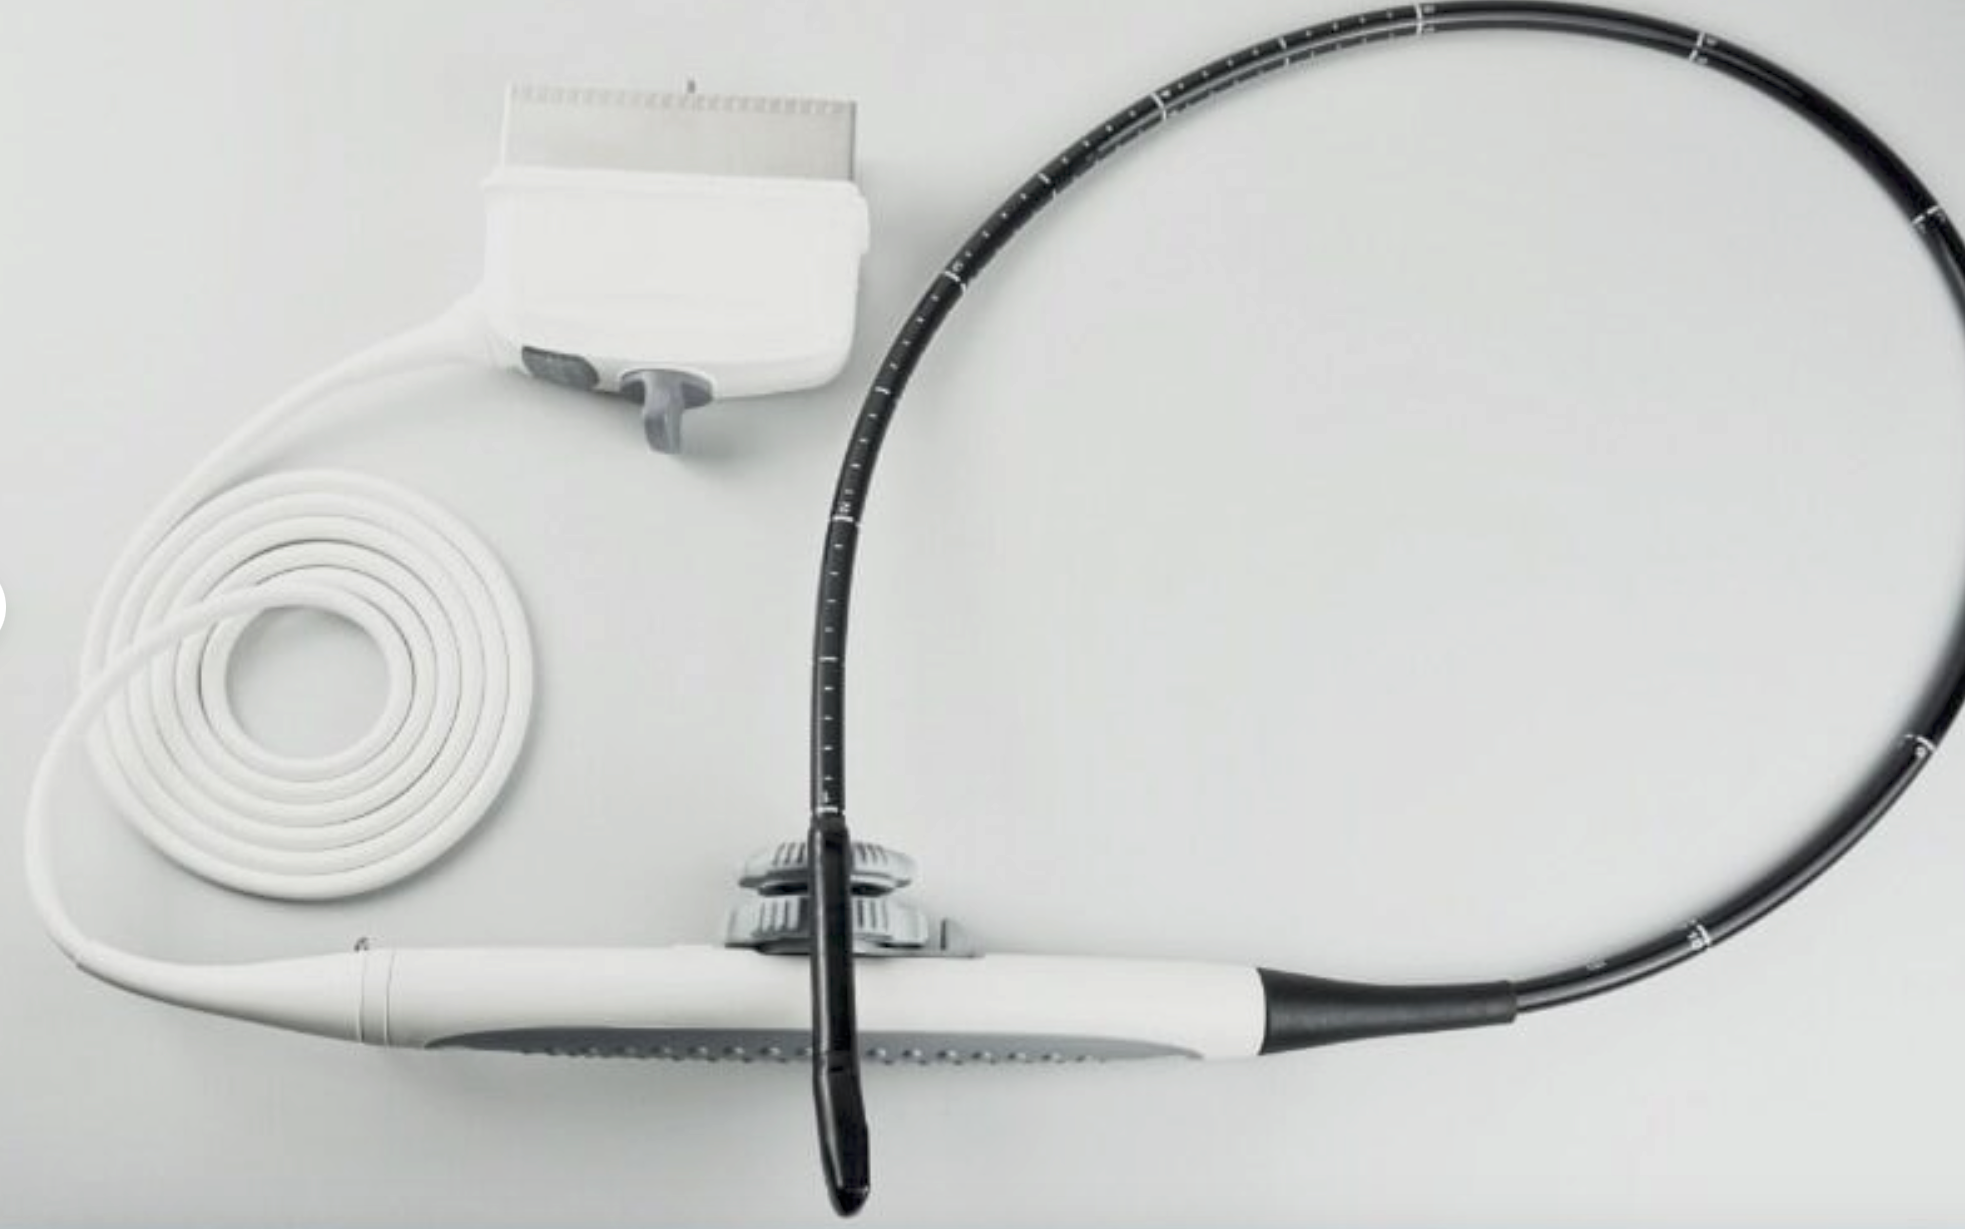

Acuson L382 3.5 MHz Linear Array Ultrasound Transducer Probe.USED TESTED

The Acuson L382 3.5 MHz Linear Array Ultrasound Transducer Probe is a used, tested, and fully functional device designed for high-resolution imaging. Ideal for vascular, musculoskeletal, and superficial tissue assessments, the 3.5 MHz frequency provides excellent detail for imaging of smaller structures. This transducer is compatible with Acuson ultrasound systems and is designed to deliver clear, reliable results for diagnostic applications. Despite being a used unit, it has been thoroughly tested to ensure it meets performance standards. It's a cost-effective solution for healthcare professionals seeking a quality ultrasound probe for detailed imaging.